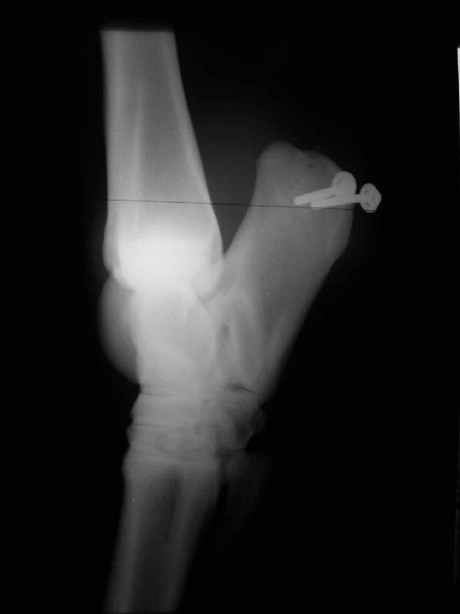

Luxation der Beugesehne (Achillessehne) vom Fersenbein

Abgleitsperre mittels Spongiosaschrauben